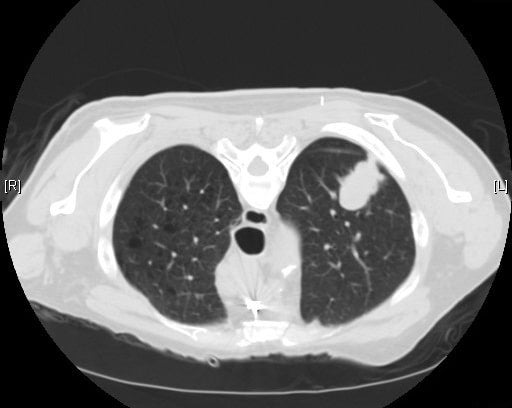

Based on the national and international evidence, a [lung cancer] screening program using biennial low dose computed tomography in asymptomatic high-risk Australians could detect cancers in their early stages when treatment is most likely to be successful. Such a screening program would save lives, reduce lung cancer mortality in Australia by 20% in the screened population, and improve the survival and quality of life of Australians affected by lung cancer.